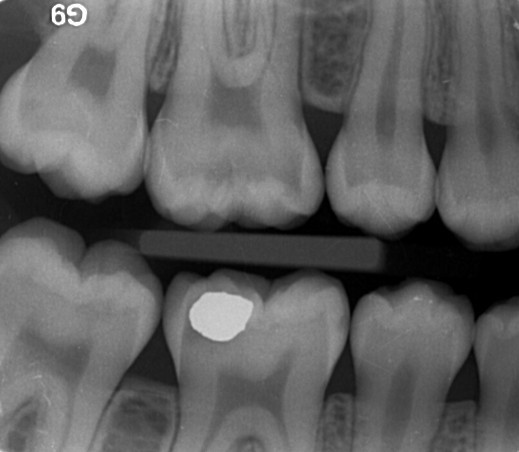

Et mesterstykke i bedrag. Deans undersøgelser fra 1942 af sammenhængene mellem caries, fluor og dental fluorose i 13 amerikanske byer. Af uransagelige årsager er 0-punktet for fluorose henlagt til en cariesforekomst på 3 DMF-T. Herved opnås et skæringspunkt mellem de to linier svarende til et fluoridindhold i drikkevandet på 1 ppm (det såkaldt optimale fluorindhold). Ingen af byerne havde en gennemsnitlig DMF-T blandt 12 til 14 årige på mindre end 2. I dagens Danmark betragtes dette som en meget høj cariesforekomst. Årsagen er at mundhygiejnen i USA i 1942 var ekstrem dårlig, en faktor som der slet ikke er taget højde for.